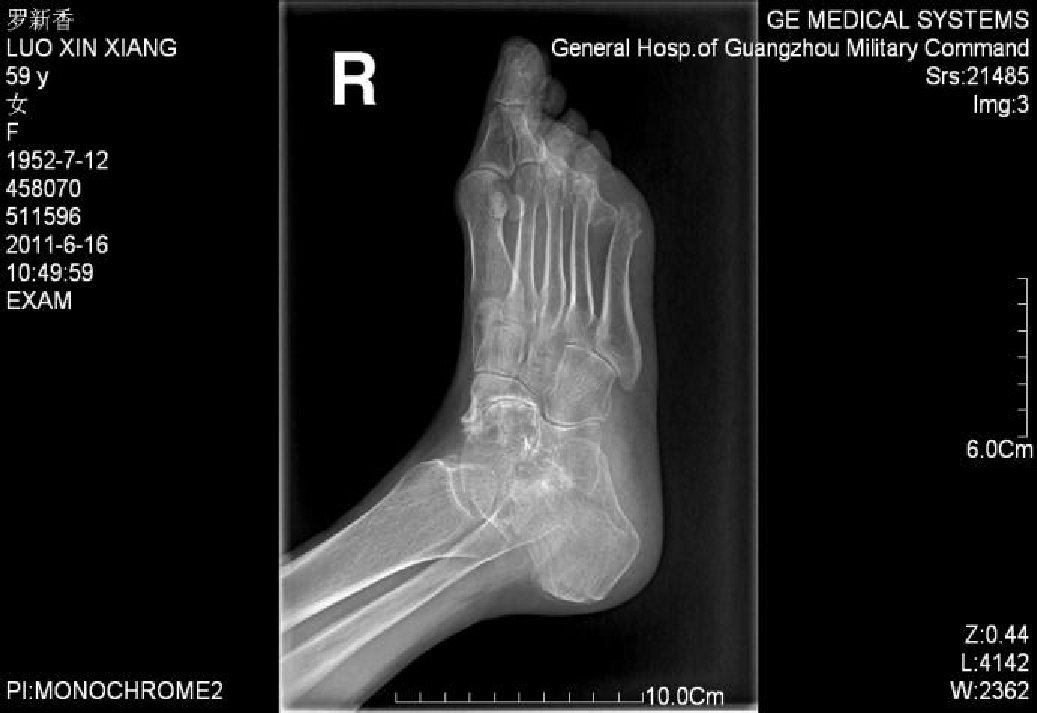

2:侧位片观察和测量第1跖骨倾斜角  第1跖骨中轴线和地面水平线的夹角。正常约为15°。此角对于术前选择手术方式意义不大,可以作为术后判断第1跖骨位置的一个参考。

第1跖骨相对于距骨关系  比较距骨颈中轴线和第1跖骨中轴线的关系。正常两线应当重叠。跖骨线位于距骨线背侧时,表示跖骨头背伸。跖骨线位于距骨线跖侧时,表示跖骨头跖屈。

第1、2跖骨关系  分别画出第1、2跖骨干背侧缘,比较两者之间的关系。正常时,两重叠或平行。在第1跖骨头背伸或跖屈时,可见两者成角。